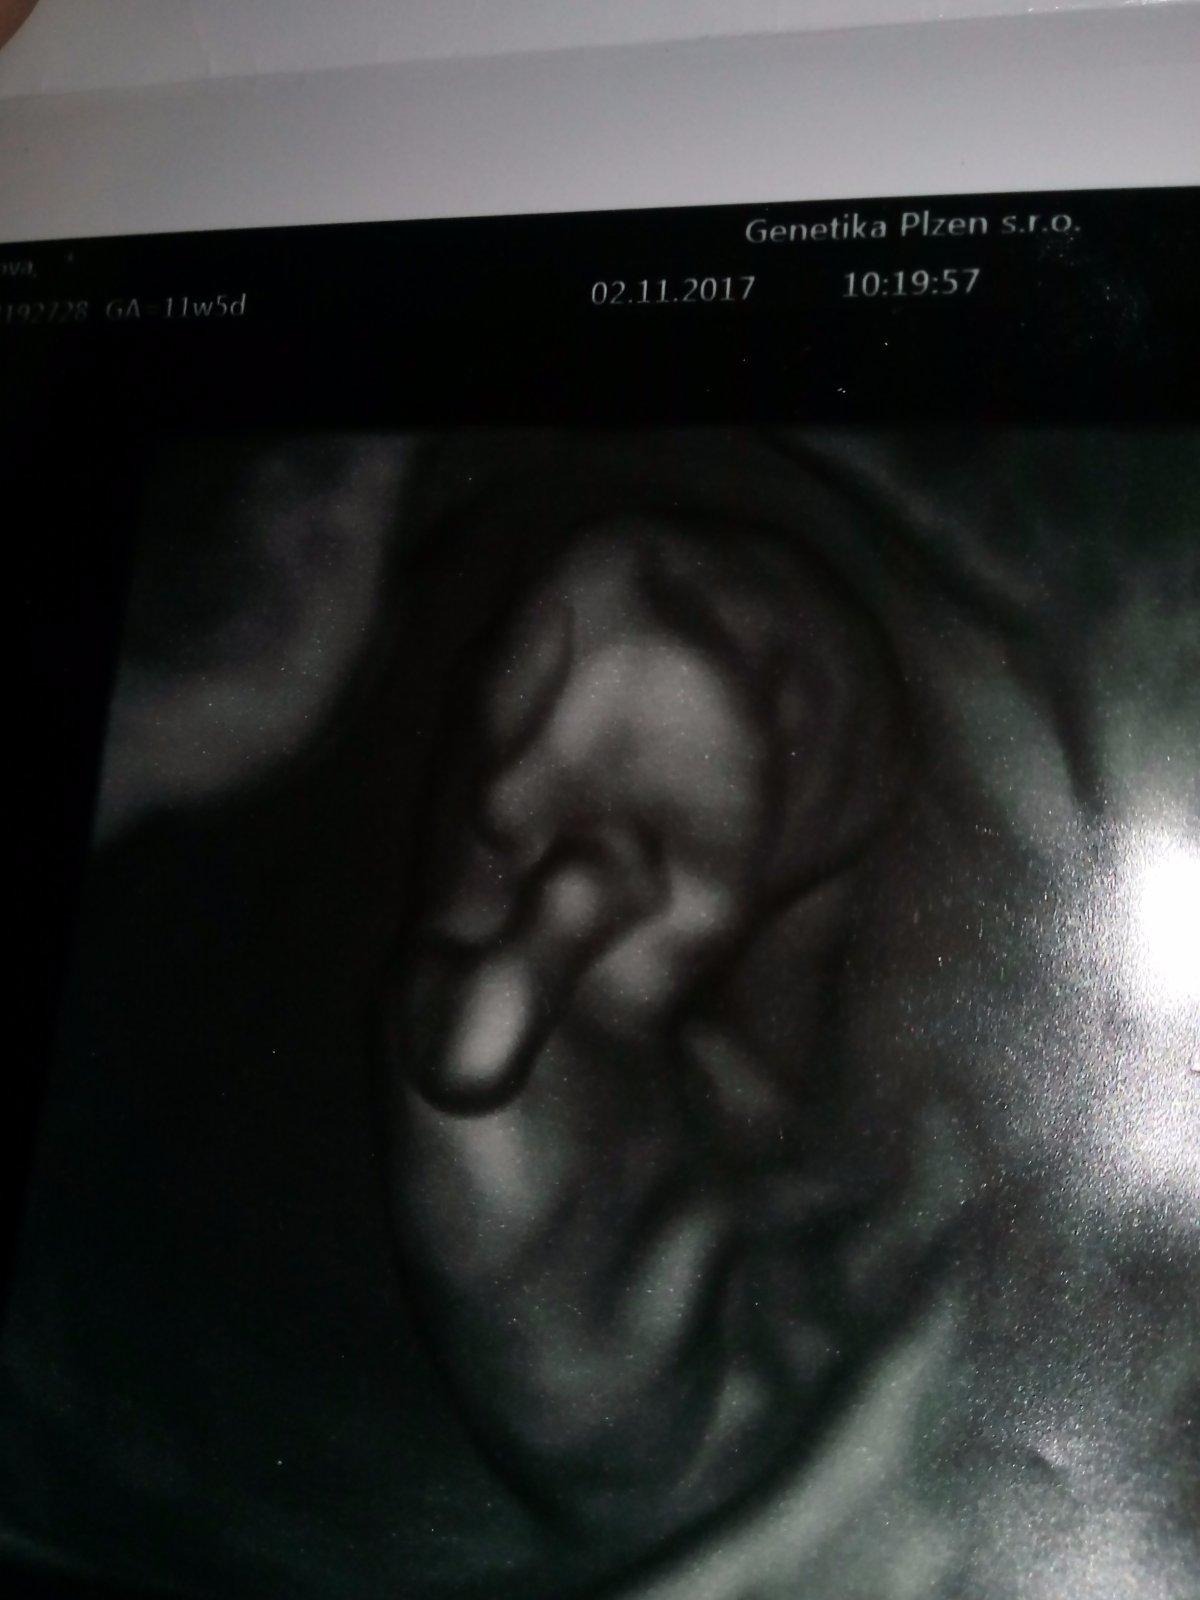

@lenka_1981 Ahoj, ve 13tt lze poznat jen podle sklonu pohl. výběžku, takže je třeba mít fotku z profilu, z této to bohužel poznat nepůjde..